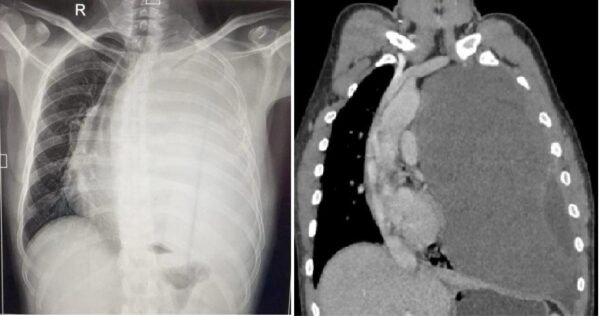

विक्रम सिंह को छाती में दर्द की समस्या जुलाई 2023 में शुरू हुई थी। लगभग एक साल से वह छाती में होने वाले तीब्र दर्द से परेशान थे। आस-पास के अस्पतालों से लेकर उन्होंने राज्य के अन्य बड़े अस्पतालों में भी अपनी बीमारी का परीक्षण कराया। थोरेसिक सर्जन उपलब्ध नहीं होने की वजह से जब कई अस्पतालों ने हाथ खड़े कर दिए तो विक्रम की अन्तिम उम्मीद ऋषिकेश एम्स पर आकर टिक गई। पिछले महीने एम्स पहुंचने पर विक्रम ने सीटीवीएस विभाग के चिकित्सकों को अपनी समस्या से अवगत कराया। सीटी स्कैन कराने पर डॉक्टरों ने जब रिपोर्ट देखी तो पता चला कि मरीज के बाएं फेफड़े पर एक विशालकाय ट्यूमर बन गया है, जो उस फेफड़े को पूरी तरह दबाने के साथ-साथ कभी भी दाएं फेफड़े को भी अपनी चपेट में ले सकता था।

एम्स के हृदय छाती एवं रक्त-वाहिनी शल्य चिकित्सा (सी.टी.वी.एस.) विभागाध्यक्ष डॉ. अंशुमान दरबारी ने बताया कि हाई रिस्क में होने के बाद भी ट्यूमर निकालने के लिए ओपन सर्जरी करने का निर्णय लिया गया। डॉ. दरबारी ने बताया कि  बीती 11 जून को उनकी कुशल टीम ने सर्जरी द्वारा मरीज की छाती खोलकर एक ही बार में पूरा ट्यूमर निकाल दिया। सर्जरी करने वाली टीम में डॉक्टर दरबारी के अलावा सीटीवीएस विभाग के डॉक्टर अविनाश प्रकाश और एनेस्थेसिया विभाग के डॉ. अजय कुमार का विशेष योगदान रहा। ग्रसित मरीज की छाती से निकाला गया ट्यूमर 22×20 सेमी. और 3.2 किलोग्राम वजन का है।